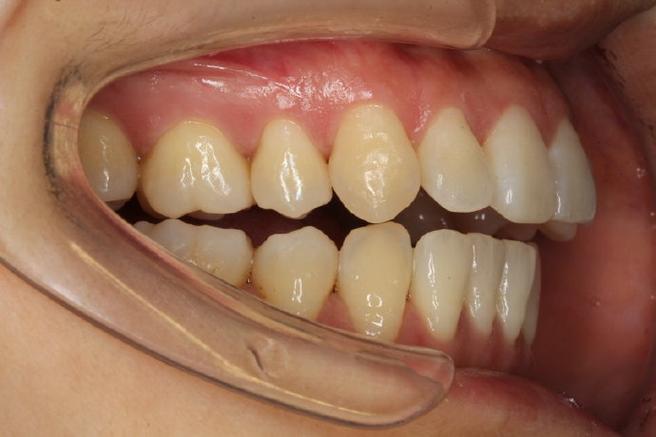

正畸前的全面评估是关键,临床检查需关注张口度(正常约3.5-4.5cm)、有无弹响及疼痛点、下颌运动轨迹是否对称;影像学检查中,MRI可清晰显示关节盘位置、形态及髁突活动度,CBCT能观察骨结构有无破坏(如髁突吸收、关节间隙狭窄);咬合分析需排查早接触、咬合干扰等异常;肌电图可辅助评估咀嚼肌功能状态,根据评估结果,医生需判断关节问题是否为继发于咬合紊乱,正畸能否成为治疗环节之一,或是否需先处理关节问题。